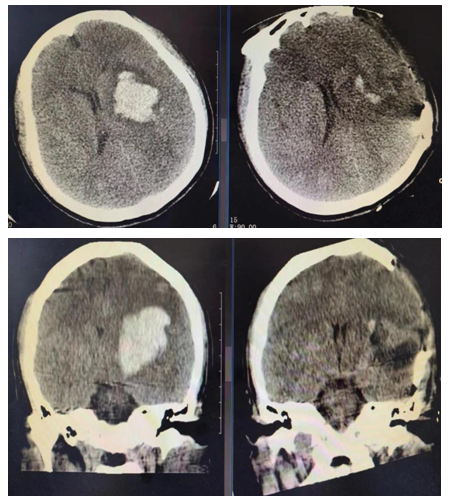

患者为44岁女性,因“突发意识不清7小时”入院。来院后行颅脑CT平扫示左侧基底节区脑出血,量约42ml。患者意识呈浅昏迷,颅内出血量大、血肿位置较深、中线偏移明显。根据临床表现,行全面检查,并充分评估,患者行神经内镜手术指征明确,无禁忌症。李帅医生于当天夜里第一时间紧急指导县黑料网

神经外科团队为患者在全麻下行神经内镜辅助下颅内血肿清除术。手术过程顺利,术后患者生命体征平稳,复查颅脑CT平扫可见血肿清除满意,止血良好。